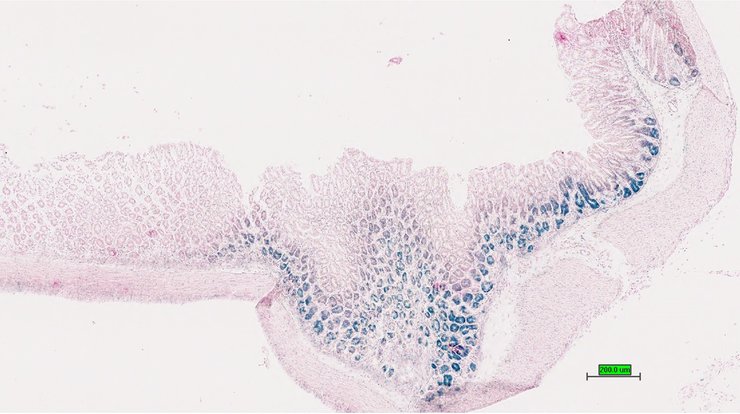

TS28: esophagus Present UC Davis_1888867

Specimen UC Davis_1888868: postnatal adult; Fndc3btm1.1(KOMP)Vlcg/Fndc3b+ (more )

Structure Level Pattern Image Note

TS28: esophagus Present UC Davis_1888868